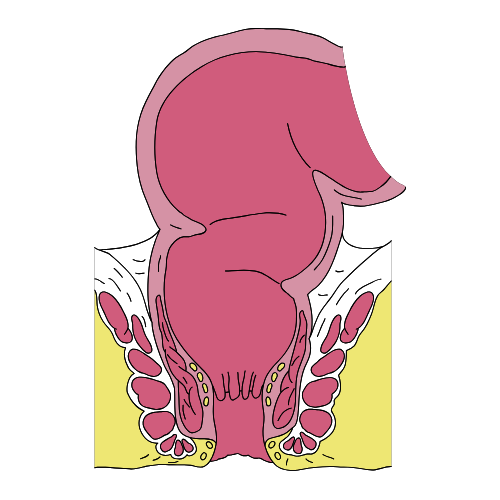

10. Hermoroid adalah pembengkakan pembuluh darah vena diekitar anus. Hemoroid umumnya terjadi pada orang – orang yang sering duduk dalam waktu yang lama dan pada orang yang menderita sembelit.